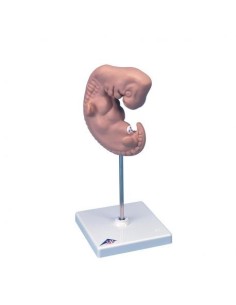

Dal cranio in 22 parti con incastri magnetici ai modelli di colonna vertebrale, da quelli di articolazioni a quelli di cuore, ogni pezzo della nostra collezione è progettato per un’immersione totale nello studio dell’anatomia umana. I nostri modelli, realizzati tramite scansioni di ossa vere, garantiscono un’esperienza tattile autentica e una fedeltà di peso quasi identica agli originali.

Essenziali per studenti e professionisti, i nostri modelli anatomici sono strumenti didattici che permettono di osservare le strutture anatomiche con precisione, eliminando la necessità di dissezioni o studi invasivi. Sono inoltre utili per spiegare ai pazienti le patologie, rendendo la comunicazione più efficace e risparmiando tempo prezioso.